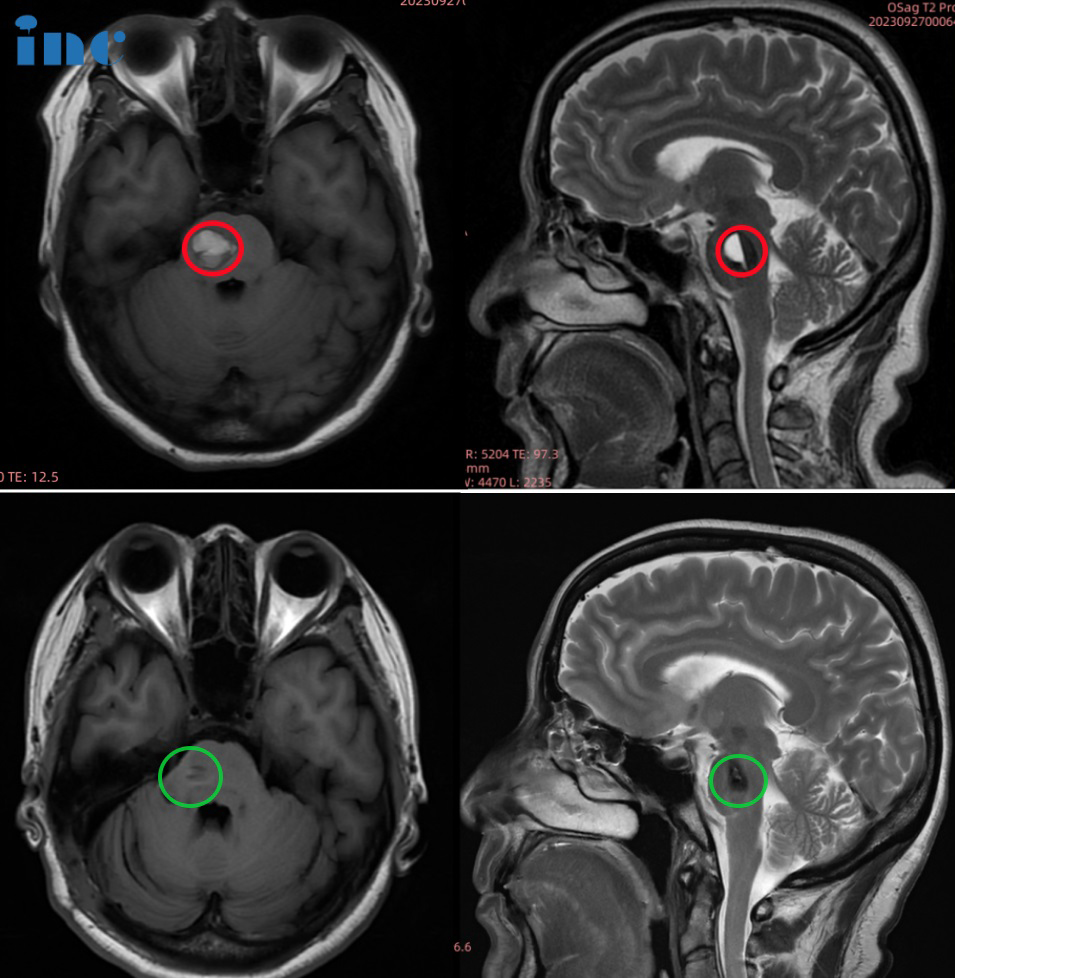

▼金女士术后3个月影像对比

52岁的金女士脑干海绵状血管瘤多次出血,病灶大小两年内迅速增长,出血量一次也一次变大,出血时间间隔也越来越短,导致头晕、眼肌痉挛、耳朵不适等问题,而除了脑干海绵状血管瘤,面神经处的血管分叉形成“剪刀效应”,已经把面神经夹住。因为压迫时间很长,导致了严重的面肌痉挛。

2023年9月28日,巴教授于苏州大学附属独墅湖医院为金女士顺利手术,巴教授成功为金女士取出了这颗脑干位置的不定时炸弹,无任何新发神经功能损伤,同时巴教授也成功进行了面神经解压术,解决了金女士面肌痉挛的问题。

影像对比提示金女士的海绵状血管瘤增大,出血量逐渐增多

术前影像:面神经受压迫